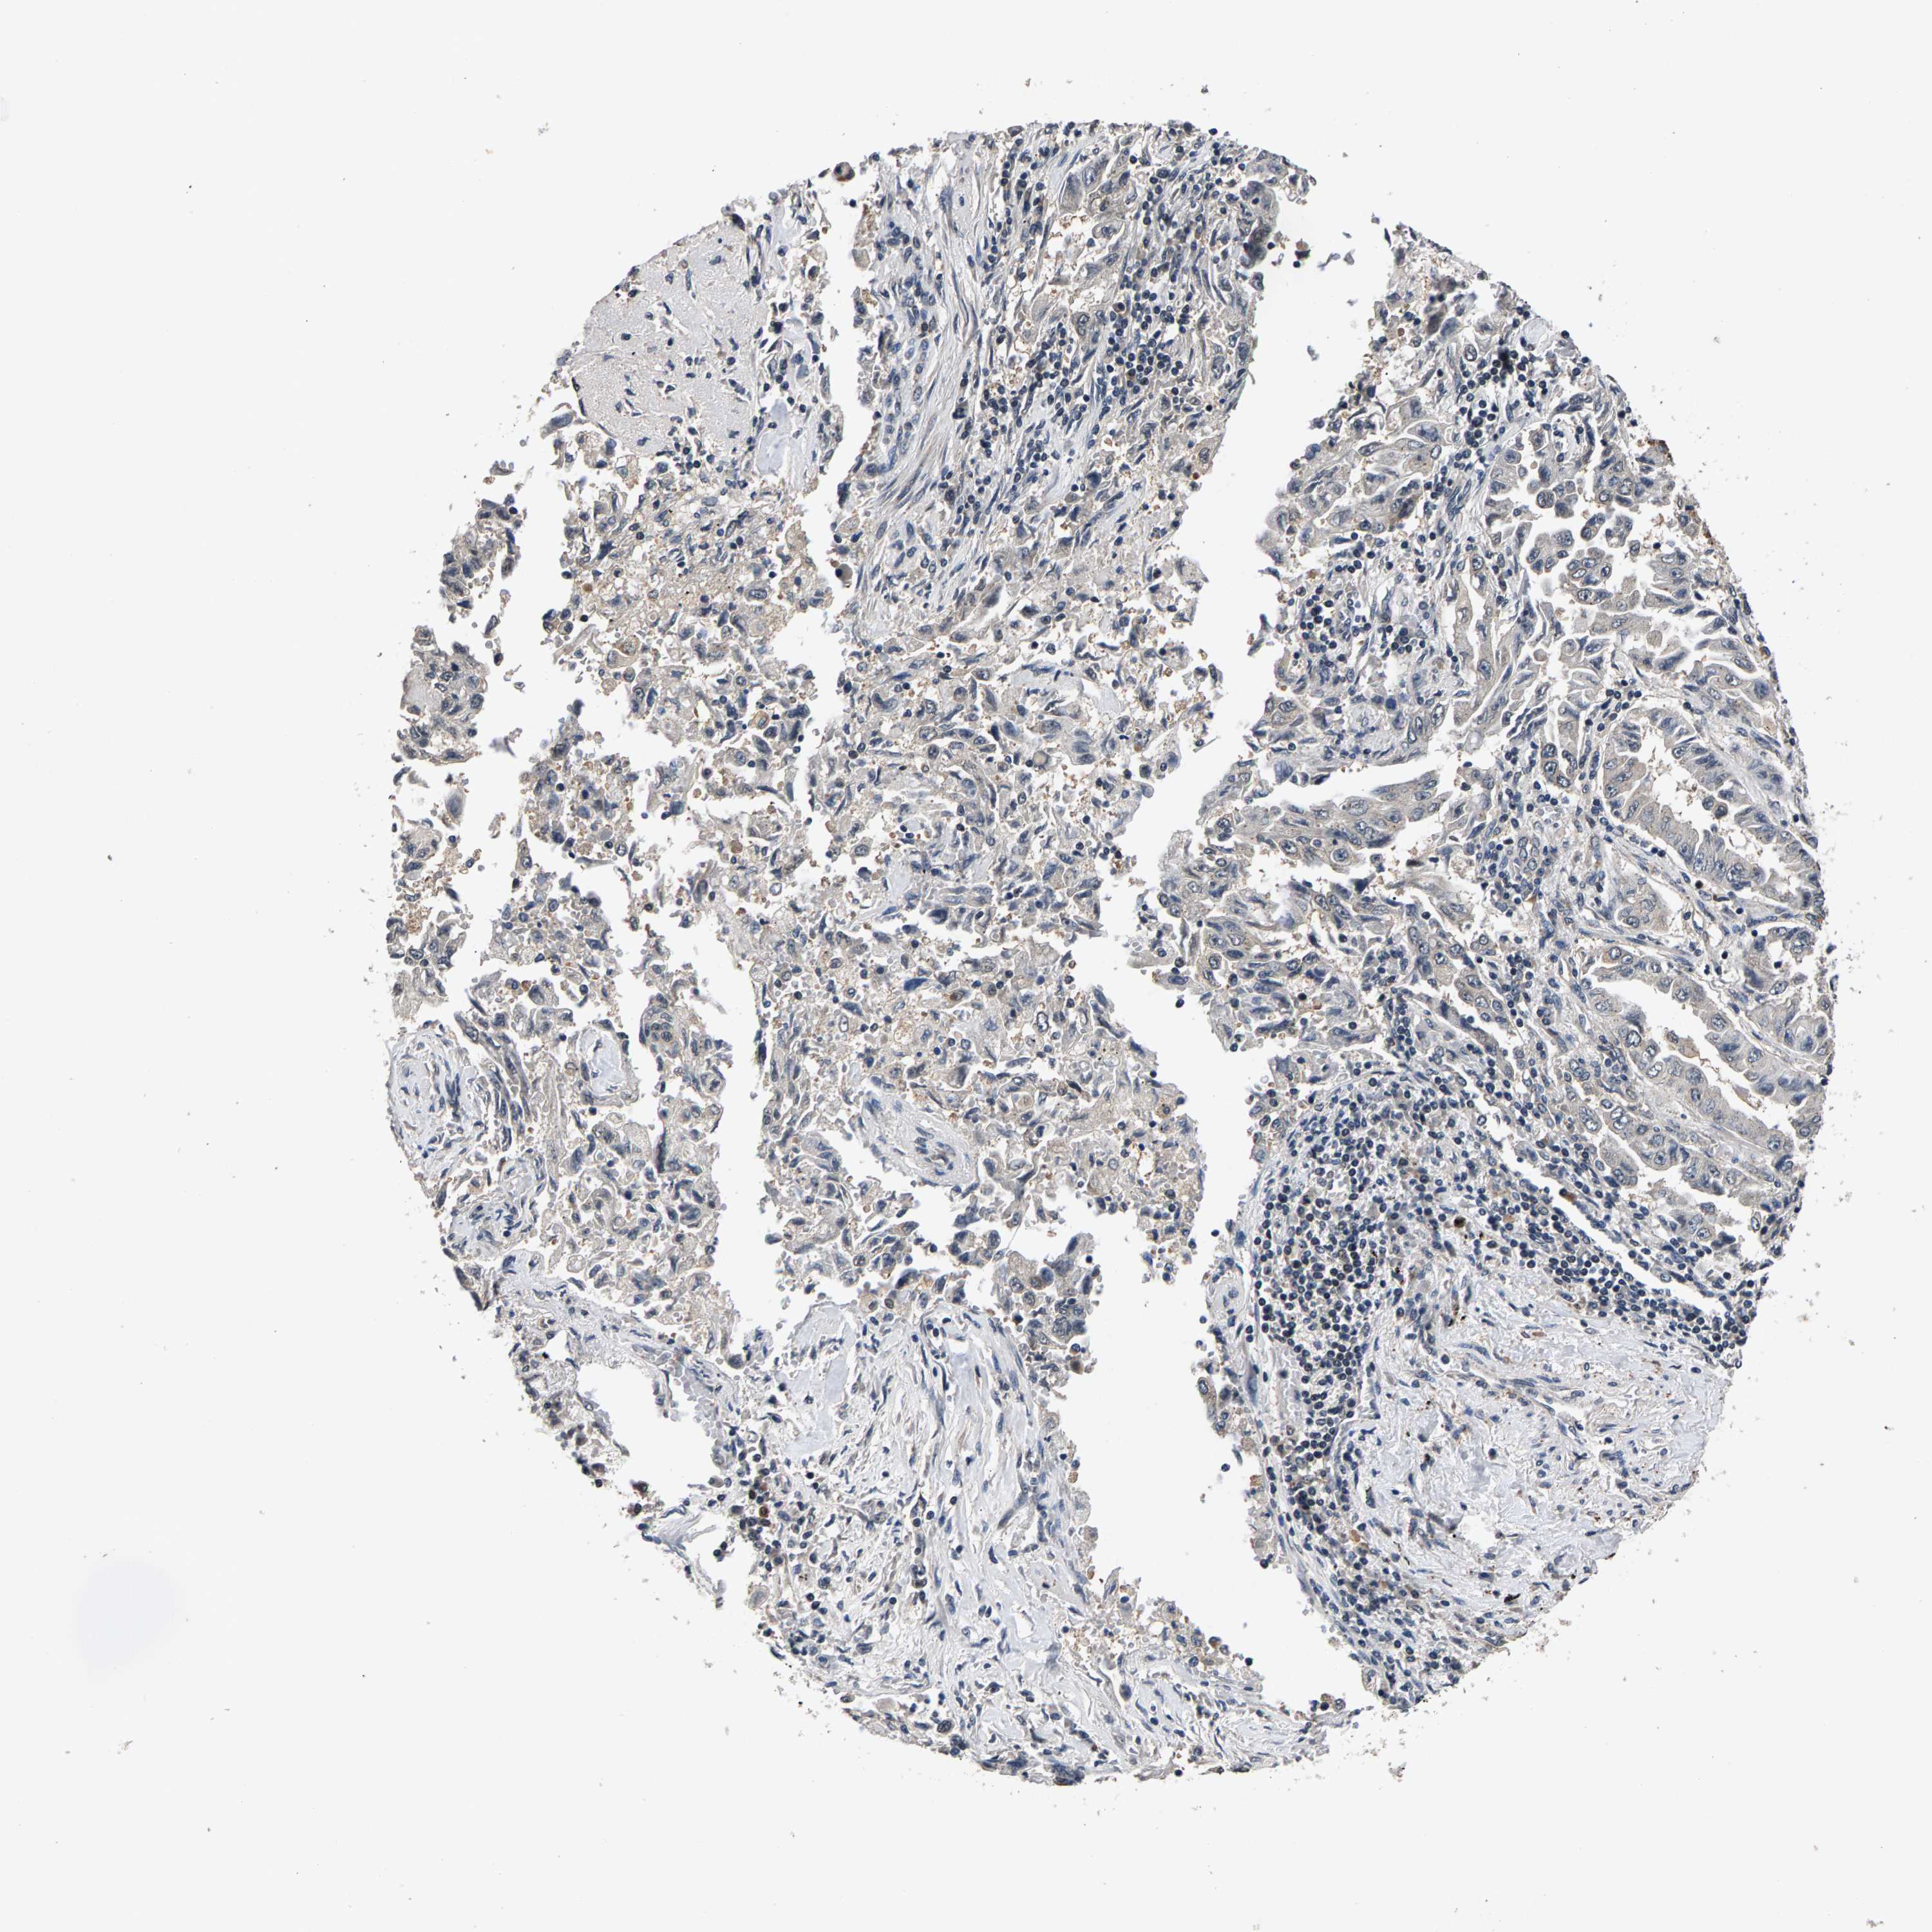

LUNG ADENOCARCINOMA (VALIDATION) - Interactive survival scatter ploti

RBM33 is not prognostic in Lung Adenocarcinoma (validation)

Best expression cut offi

: 15.5

P scorei

N/A

Average pTPM 18.4

Number of samples 105